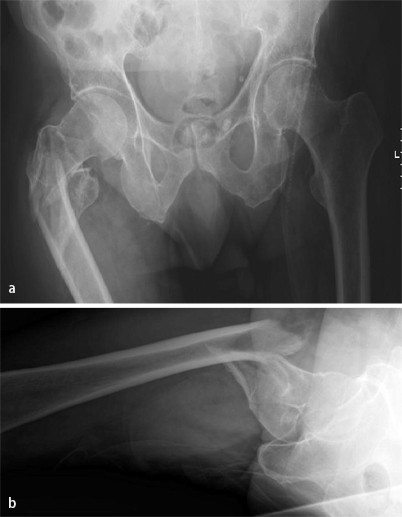

Welche Aussage zur Behandlung der in Abb. 2a, b dargestellten intertrochantären Femurfraktur ist zutreffend?

Abb. 2

figure 2

a Im a.-p. -Strahlengang, b „Cross-table“-Aufnahme

Diese A1-Fraktur ist als dringlich anzusehen und sollte zeitnah versorgt werden.

Bei einer derartigen Fraktur ist eine Versorgung mithilfe der DHS die beste Option, da die laterale Wand intakt scheint.

Aufgrund der Schaftkomponente ist diese Fraktur gut für einen retrograden Nagel zugänglich.

Bei derartigen Frakturen ist eine offene Reposition unter Zuhilfenahme von Cerclagen und die Einbringung eines langen intramedullären Nagels eine sehr gute Therapieoption.

Die sekundäre Dynamisierung stellt bei derartigen Frakturen keine Therapieoption dar.